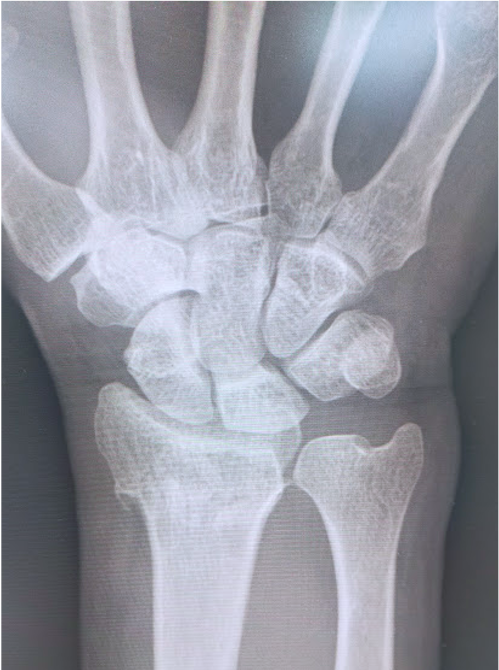

橈骨遠位端骨折に対する骨接合術